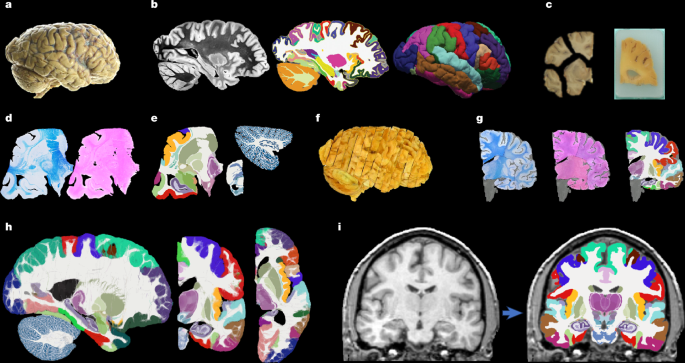

Hemispheres from five individuals (including half of the cerebrum, cerebellum and brainstem), were used in this study, following informed consent to use the tissue for research and the ethical approval for research by the National Research Ethics Service Committee London – Central. All hemispheres were fixed in 10% neutral buffered formalin (Fig. 1a). The laterality and demographics are summarized in Supplementary Table 1; the donors were neurologically normal, but one case had an undiagnosed, asymptomatic tumour (diameter roughly 10 mm) in the white matter, adjacent to the pars opercularis. This tumour did not pose issues in any of the processing steps described below.

Before dissection, the hemispheres were scanned on a 3-T Siemens MAGNETOM Prisma scanner. The specimens were placed in a container filled with Fluorinert (perfluorocarbon), a proton-free fluid with no MRI signal that yields excellent ex vivo MRI contrast and does not affect downstream histological analysis58. The MRI scans were acquired with a T2-weighted sequence (optimized long echo train 3D fast spin echo59) with the following parameters: TR = 500 ms, TEeff = 69 ms, BW = 558 hertz per pixel, echo spacing = 4.96 ms, echo train length = 58, 10 averages, with 400-μm isotropic resolution, acquisition time for each average = 547 s, total scanning time = 91 min. These scans were processed with a combination of SAMSEG35 and the FreeSurfer 7.0 cortical stream51 to bias-field-correct the images, generate rough subcortical segmentations and obtain white matter and pial surfaces with corresponding parcellations according to the Desikan–Killiany atlas29 (Fig. 1b).

After MRI scanning, each hemisphere is dissected to fit into standard 74 mm × 52 mm cassettes. First, each hemisphere was split into cerebrum, cerebellum and brainstem. Using a metal frame as a guide, these were subsequently cut into 10-mm-thick slices in coronal, sagittal and axial orientation, respectively. These slices were photographed inside a rectangular frame of known dimensions for pixel size and perspective correction; we refer to these images as ‘whole slice photographs’. Although the brainstem and cerebellum slices all fit into the cassettes, the cerebrum slices were further cut into as many blocks as needed. ‘Blocked slice photographs’ were also taken for these blocks (Fig. 1c, left).

After standard tissue processing steps, each tissue block was embedded in paraffin wax and sectioned with a sledge microtome at 25-μm thickness. Before each cut, a photograph was taken with a 24 MPx Nikon D5100 camera (ISO = 100, aperture = f/20, shutter speed = automatic) mounted right above the microtome, pointed perpendicularly to the sectioning plane. These photographs (henceforth ‘blockface photographs’) were corrected for pixel size and perspective using fiducial markers. The blockface photographs have poor contrast between grey and white matter (Fig. 1c, right) but also negligible nonlinear geometric distortion, so they can be readily stacked into 3D volumes. A two-dimensional convolutional neural network (CNN) pretrained on the ImageNet dataset60 and fine-tuned on 50 manually labelled examples was used to automatically produce binary tissue masks for the blockface images.

We mounted on glass slides and stained two consecutive sections every N (see below), one with H&E and one with LFB (Fig. 1d). The sampling interval was N = 10 (that is, 250 μm) for blocks that included subcortical structures in the cerebrum, medial structures of the cerebellum or brainstem structures. The interval was N = 20 (500 μm) for all other blocks. All stained sections were digitized with a flatbed scanner at 6,400 DPI resolution (pixel size 3.97 μm). Tissue masks were generated using a two-dimensional CNN similar to the one used for blockface photographs (pretrained on ImageNet and fine-tuned on 100 manually labelled examples).

Dense labelling of histology

To roughly initialize the 3D reconstruction, we relied on the stacks of blockface photographs. Specifically, we used our previously presented hierarchical joint registration framework23 that seeks to (1) align each block to the MRI with a similarity transform, by maximizing the normalized cross-correlation of their intensities while (2) discouraging overlap between blocks or gaps in between, by means of a differentiable regularizer. The similarity transforms allowed for rigid deformation (rotation, translation), as well as isotropic scaling to model the shrinking due to tissue processing. The registration algorithm was initialized with transforms derived from the whole slice, blocked slice and blockface photographs (see details in ref. 26). The registration was hierarchical in the sense that groups of transforms were forced to share the same parameters in the earlier iterations of the optimization, to reflect our knowledge of the cutting procedure. In the first iterations, we clustered the blocks into three groups: cerebrum, cerebellum and brainstem. In the following iterations, we clustered the cerebral blocks that were cut from the same slice and allowed translations in all directions, in-plane rotation and global scaling. In the final iterations, each block alignment was optimized independently. The numerical optimization used the LBFGS algorithm63. The approximate average error after this procedure was about 2 mm (ref. 23). A sample 3D reconstruction is shown in Fig. 1f.

Running SbR for each stain and section independently (that is, LFB to resampled MRI and H&E to resampled MRI) yields a reconstruction that is jagged and sensitive to folds and tears. One alternative is to register each histological section to each neighbour directly, which achieves smooth reconstructions but incurs the so-called ‘banana effect’: that is, a straightening of curved structures14. We have proposed a Bayesian method that yields smooth reconstructions without the banana effect25. This method follows an overconstrained strategy by computing registrations between LFB and MRI, H&E and MRI, H&E and LFB, each LFB section and the two nearest neighbours in either direction across the stack, each H&E section and its neighbours, and each MRI slice and its neighbours. For a stack with S sections, this procedure yields 15xS-18 registrations, whereas the underlying dimensionality of the spanning tree connecting all the images is just 3xS-1. We use a probabilistic model of SVFs to infer the most likely spanning tree given the computed registrations, which are seen as noisy measurements of combinations of transforms in the spanning tree. The probabilistic model uses a Laplace distribution, which relies on L1 norms and is thus robust to outliers. Moreover, the properties of SVFs enable us to write the optimization problem as a linear program, which we solve with a standard simplex algorithm71. The result of this procedure was a 3D reconstruction that is accurate (it is informed by many registrations), robust and smooth (Figs. 1g and 2).

Every iteration of the atlas construction process comprises two steps. First, the current estimate of the atlas and the segmentations are coregistered one at a time using (1) a diffeomorphic deformation model based on SVFs parameterized by grids of control points and B-splines (as implemented in NiftyReg72), which preserves the topology of the segmentations; (2) a data term, which is the log-likelihood of the label at each voxel according to the probabilities given by the deformed atlas (with a weak Dirichlet prior to prevent logs of zero); and (3) a regularizer based on the bending energy of the field, which encourages regularity in the deformations. The second step of each iteration updates the atlas by averaging the segmentations. The procedure converged (negligible change in the atlas) after five iterations. Slices of the atlas are shown in Figs. 1h and 3.

Sample segmentations with this method can be found in Fig. 1h (in vivo) and Fig. 4 (ex vivo).